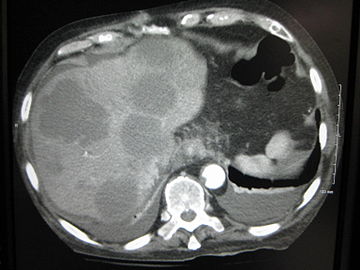

Cut surface of a liver showing multiple paler metastatic nodules originating from pancreatic cancer

This is typical route of metastasis for sarcomas, but it is also the favored route for certain types of carcinoma, such as renal cell carcinoma originating in the kidney and follicular carcinomas of the thyroid. Because of their thinner walls, veins are more frequently invaded than are arteries, and metastasis tends to follow the pattern of venous flow. That is, hematogenous spread often follows distinct patterns depending on the location of the primary tumor. For example, colorectal cancer spreads primarily through the portal vein to the liver.

There is a propensity for certain tumors to seed in particular organs. This was first discussed as the "seed and soil" theory by Stephen Paget in 1889.[28] The propensity for a metastatic cell to spread to a particular organ is termed 'organotropism'. For example, prostate cancer usually metastasizes to the bones. In a similar manner, colon cancer has a tendency to metastasize to the liver. Stomach cancer often metastasises to the ovary in women, when it is called a Krukenberg tumor.